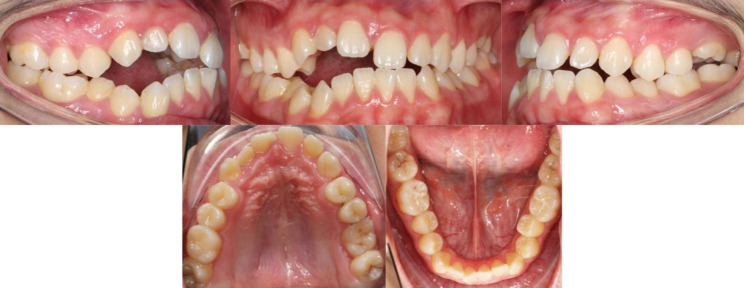

Fig. 6.

Intraoral photographs of proband at one year recall

After six months of traction, the open-bite of the anterior tooth area did not reduce. We used Mimics 15.0 to convert CBCT data into 3D models before and after orthodontic treatment and superimposed them to evaluate the three-dimensional movement of the impacted teeth. The results showed that only the third molars grew, while the anterior teeth barely moved (Fig. 5). At one year recall, we found that the degree and range of open-bite in the anterior and posterior dental areas further increased (Fig. 6).